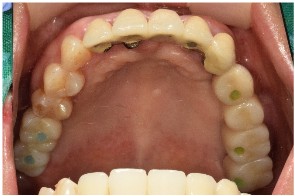

식립 후 2달이 지났을 때

아래턱 앞니와

왼쪽 어금니 부위에

심어둔 임플란트 주변으로

잇몸뼈가 잘 회복하고 있는 것을

확인하였으며

먼저 위턱 어금니와

아래턱 오른쪽 어금니의

지대주 제작을 위한

coping 인상채득을 진행하였는데요.

기공소에서 만들어온 임시 치아를 통해

최종 보철물을 제작하기 전

무너진 교합과 수직 고경을 회복시키고,

구강 근육 및 점막 안정화를 위한

시간을 가지기로 하였습니다.